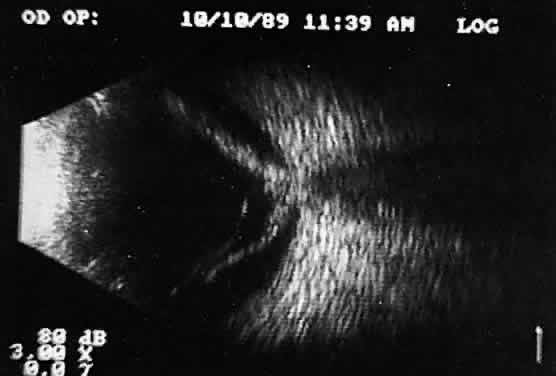

| Contact ultrasound information is best preserved on videotape, using an

oral voice-over description to identify probe positions. Occasionally, more

sophisticated split-screen special effects generators can be used, permitting

simultaneous views of the ultrasound examination with an

image of the probe position. The most common preservation methods involve

Polaroid photography of specific frozen images chosen during contact

examination. Unfortunately, these photographs document only the still

images and are not of great value for future reference or independent

analysis. Polaroid film lacks good gray scale, so subtle B-scan information

is lost. Further, contact real-time kinetic ultrasonography

is a dynamic examination that cannot be appreciated or preserved by still

photography. For immersion scanning (waterbath technique), photographs can be used to preserve information; with 35-mm gray scale, review is possible. Immersion scanning, unlike contact scanning, provides images that are derived from an anteroposterior waterbath position. A micrometer device on the examining probe permits sequential still photographic documentation. Dynamic real-time scanning is more difficult with the immersion technique, which relies on rapid multiple manual sweeps of the hand-controlled probe to provide real-time imaging. Real-time changes are best appreciated with motor-driven probes and preserved for future reference on videotape. |